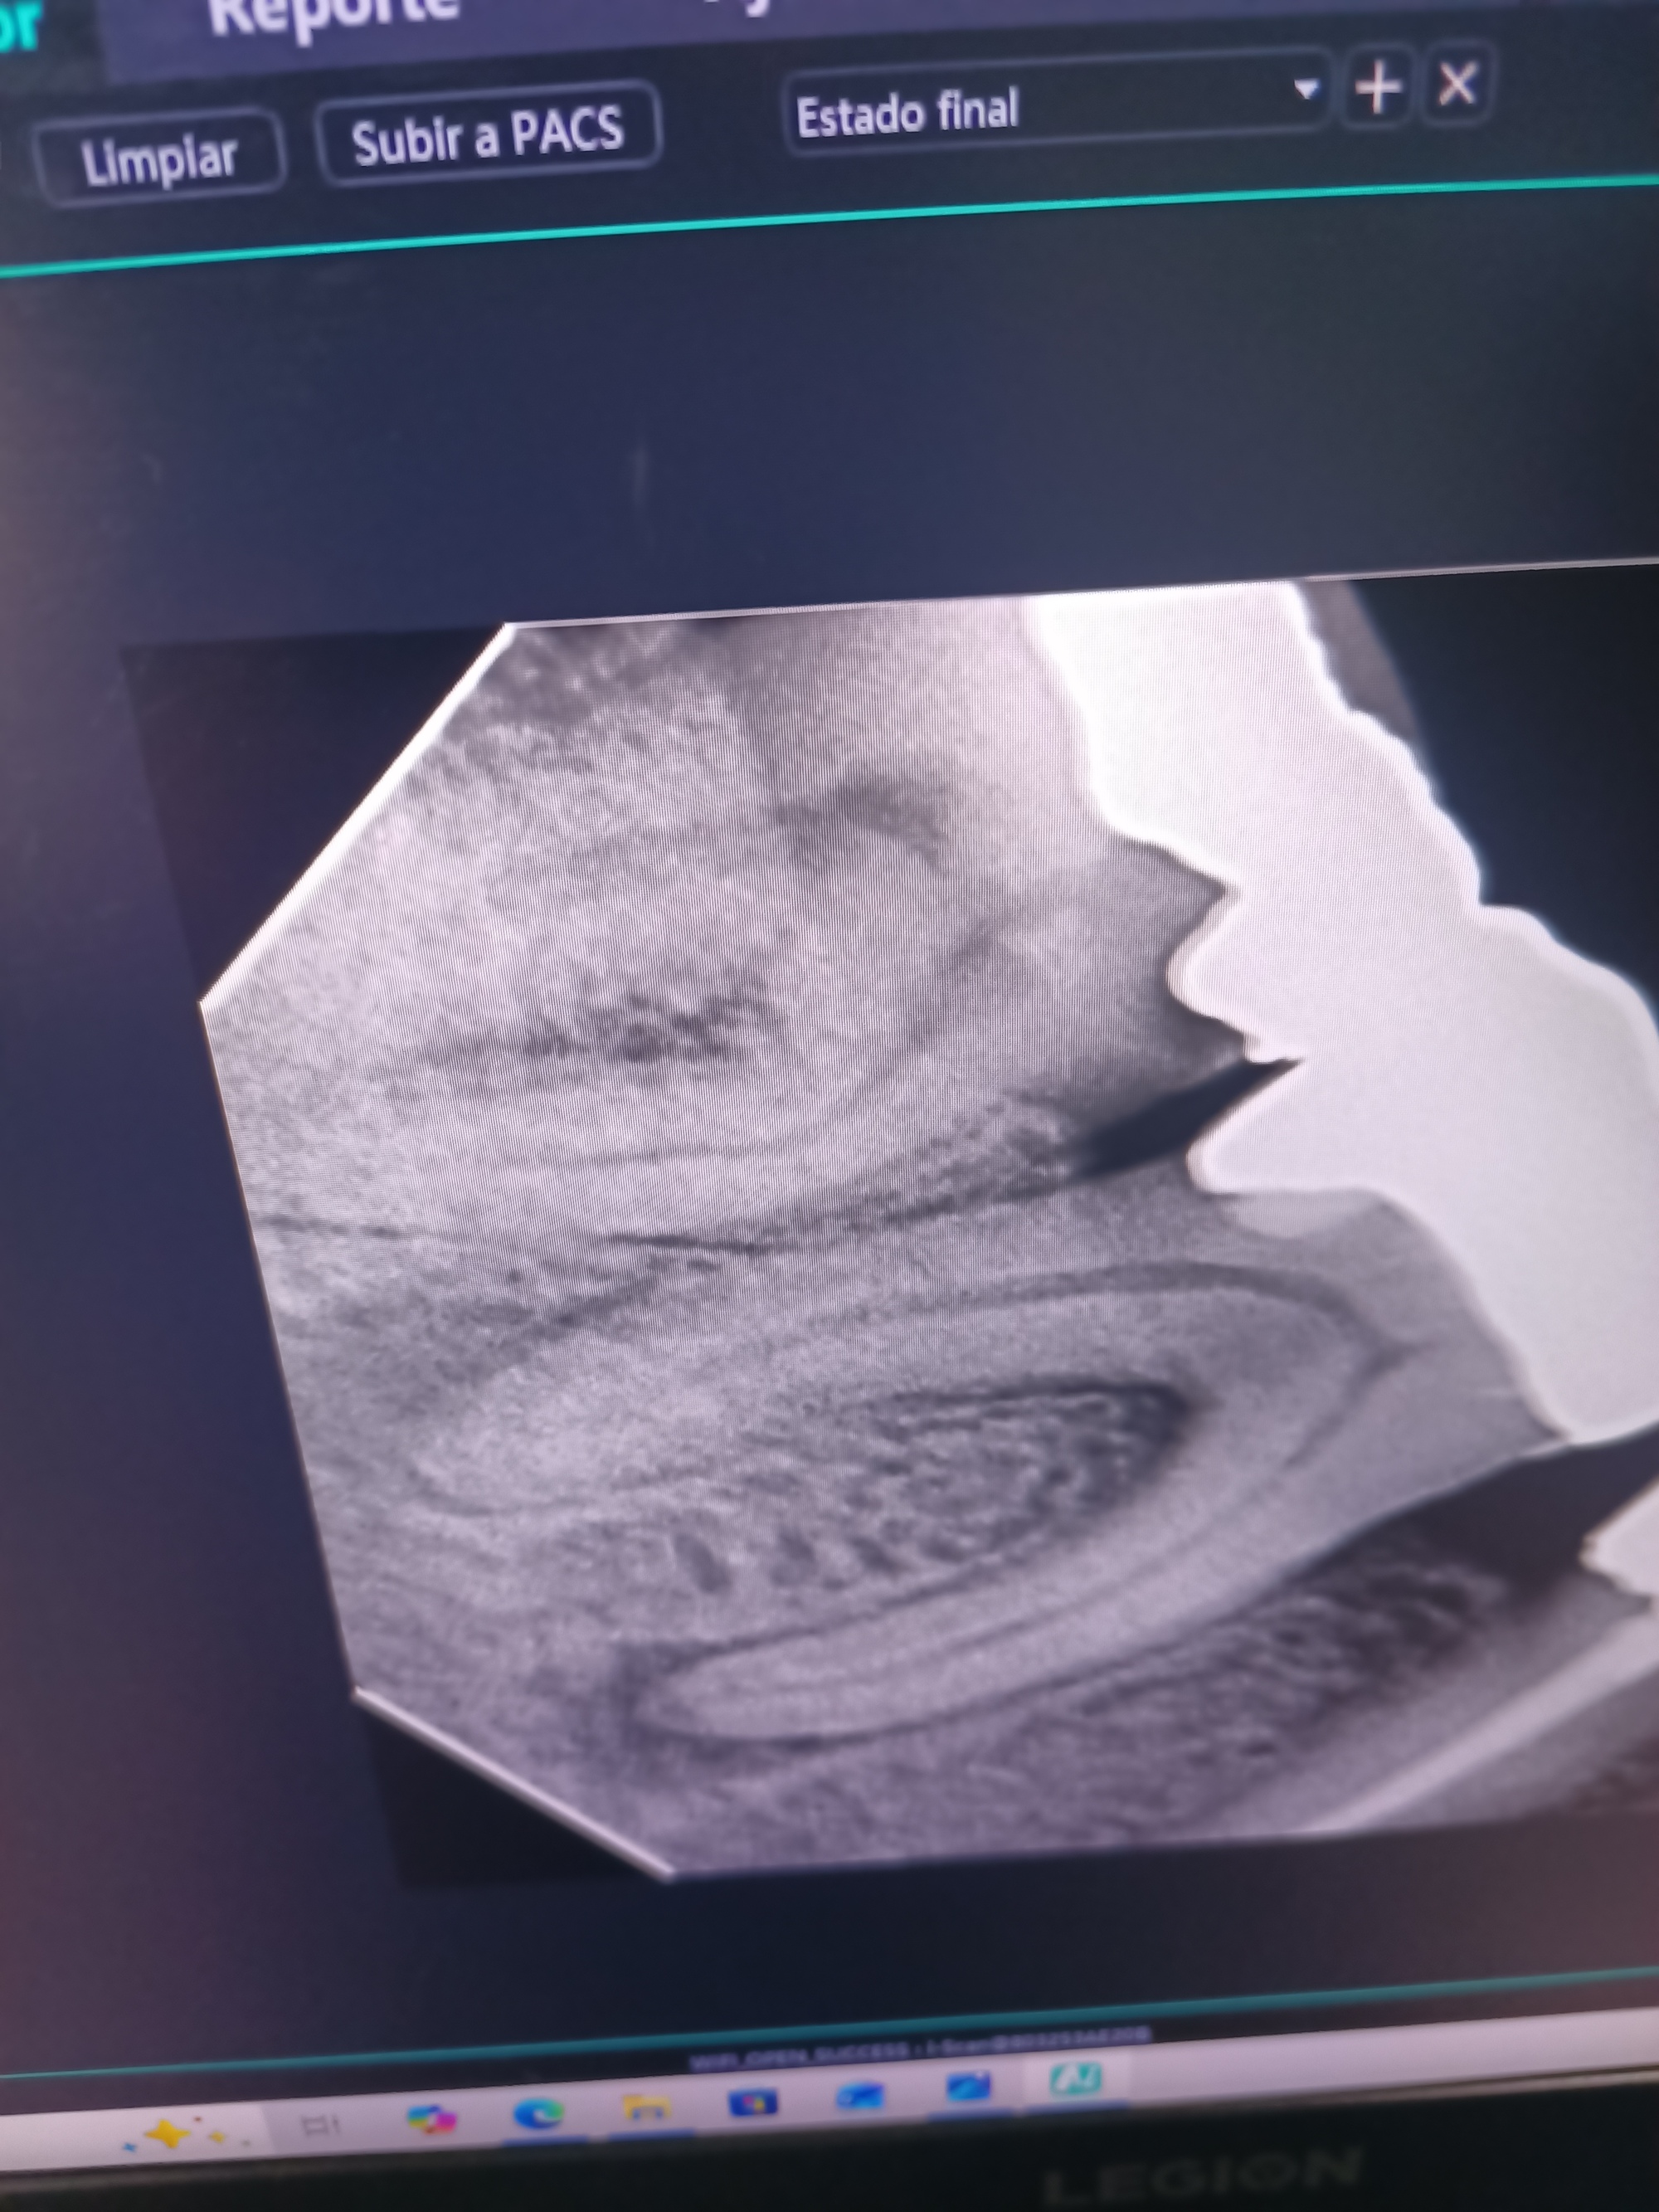

We had to wait 15 minutes for the dentist to actually arrive at the office, but when he came he took me in right away. The office was perfectly clean and stuffed with all the expected high tech equipment. One thing that I had not seen at home was a hand held x-ray gizmo, that produced immediate high resolution images on a couch-side PC. The first issue in these cases is of which tooth is actually the culprit. The dentist tried applying some extreme cold, but I had no reaction. This was in fact a needed clue. Under a crown I had a dead root, so no reaction to the cold. The pain was coming from ancillary inflammation of the area. Bottom line, I needed a root canal job.

The same PC that had shown the x-rays also helped by running Google Translate.

One thing that showed clearly was a root canal job that had been done on an adjacent tooth some years ago. I remember that one - my dentist had sent me to a distant specialist for it, and it was a bit of a big deal. But today, the thing was just going to happen immediately. I think I was lucky too. The dentist was what Michel in Nantes calls a "baby doctor". That is, a young person (like, under 40) who looks like a "baby" from the perspective of our advanced years. And in this case, the "baby" had had time to complete a specialty in endodontics!